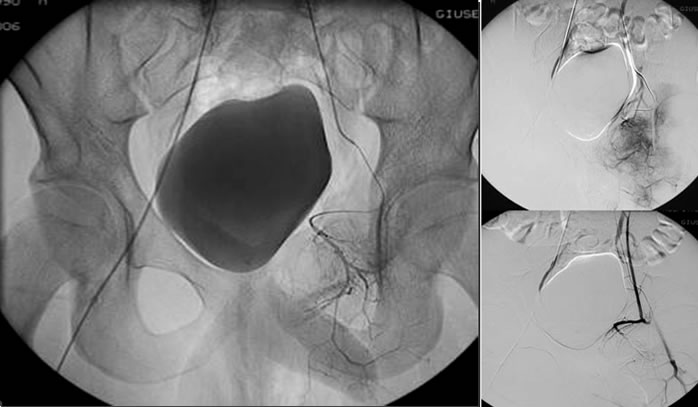

Le suddette lesioni presentano una ipervascolarizzazione patologica rifornita da uno o più vasi e sono caratterizzate dalla presenza di cavità incluse ripiene di detriti cellulari e sangue, separate da setti connettivali, sono tipici i livelli liquidi ben visibili alla TC ed alla RM.

L’embolizzazione arteriosa selettiva delle formazioni cistiche aneurismatiche, eseguita con l’utilizzo di GLUBRAN 2 (colla chirurgica) come mezzo embolizzante, blocca l’eccessivo apporto di sangue alla lesione, favorendone la guarigione. Ne consegue una ristrutturazione ossea che può essere parziale, sub-totale o totale del segmento interessato.

Adolescente di 16 anni.